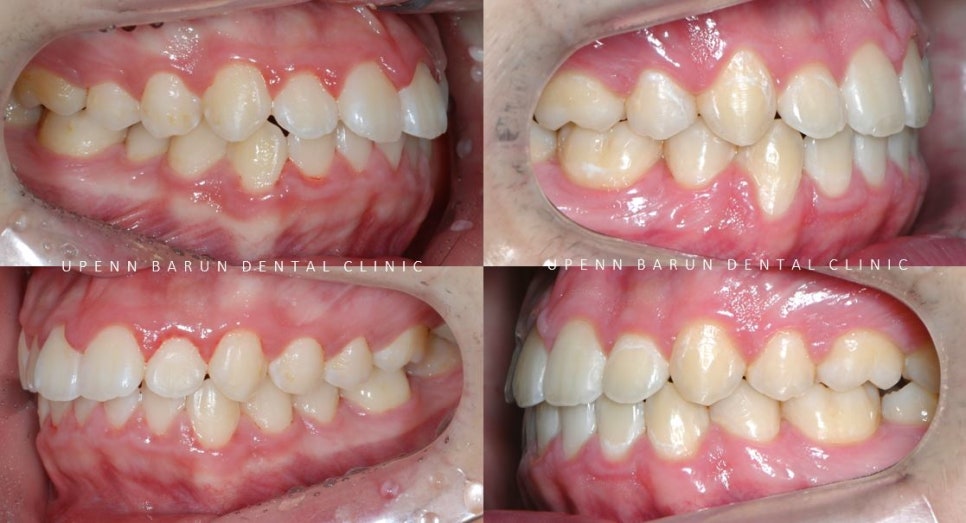

교정 전

사진에서 보시는 것처럼 윗니와 아랫니 사이에

꽤나 큰 공간이 관찰되었습니다.

악궁이 좁아 삐뚤빼뚤했던 치아들이

교정 후

발치된 공간으로 치아들이 올바르게 배열되며

교정치료가 만족스럽게 잘 마무리 되었습니다.

발치교정 후

윗니와 아랫니 사이에 공간이 현저히 줄어들면서

정상적인 교합을 만들어드렸습니다 ^^

교정치료가 끝난 후의 사진을 보시면

교정치료 전과는 다르게

도드라져 보이던 앞니의 치열과 치축이 개선되면서

가지런하게 정리되고 예쁜 스마일로

바뀐 모습을 볼 수 있습니다. ^^**